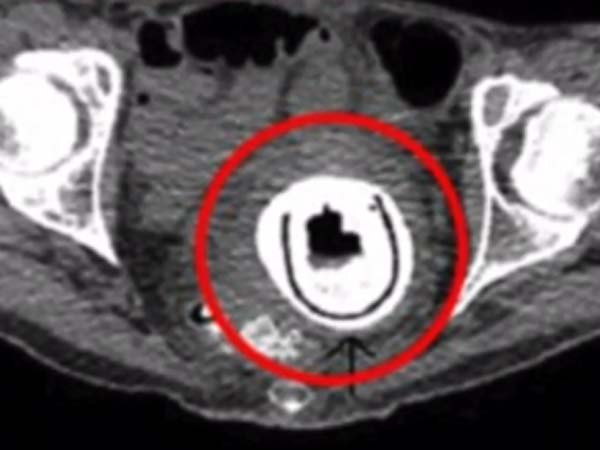

அவரைப் பரிசோதித்த டாக்டர்கள் பெண்ணுறுப்புப் பகுதியை எக்ஸ்ரே எடுத்துப் பார்த்தனர். அப்போதுதான் அவரது பெண்ணுறுப்புக்குள் செக்ஸ் பொம்மை சிக்கியிருப்பதைக் கண்டுபிடித்தனர். இதுதான் அவரை பத்து வருடமாக படாதபாடு படுத்தி வந்துள்ளது.

இந்த பொம்மை போய் சிக்கியதால் அந்தப் பெண் சிறுநீர் கழிக்கவும் அவதிப்பட்டுள்ளார். மேலும் அவரது சிறுநீரகப் பையும் வீங்கி அடைத்துக் கொண்டு விட்டது. இதனால் சிறுநீரானது மீண்டும் சிறுநீரகத்திற்கே திரும்பிப் போயுள்ளது. மேலும் சிறுநீர் போகும் பாதையும் பாதிக்கப்பட்டுள்ளது.